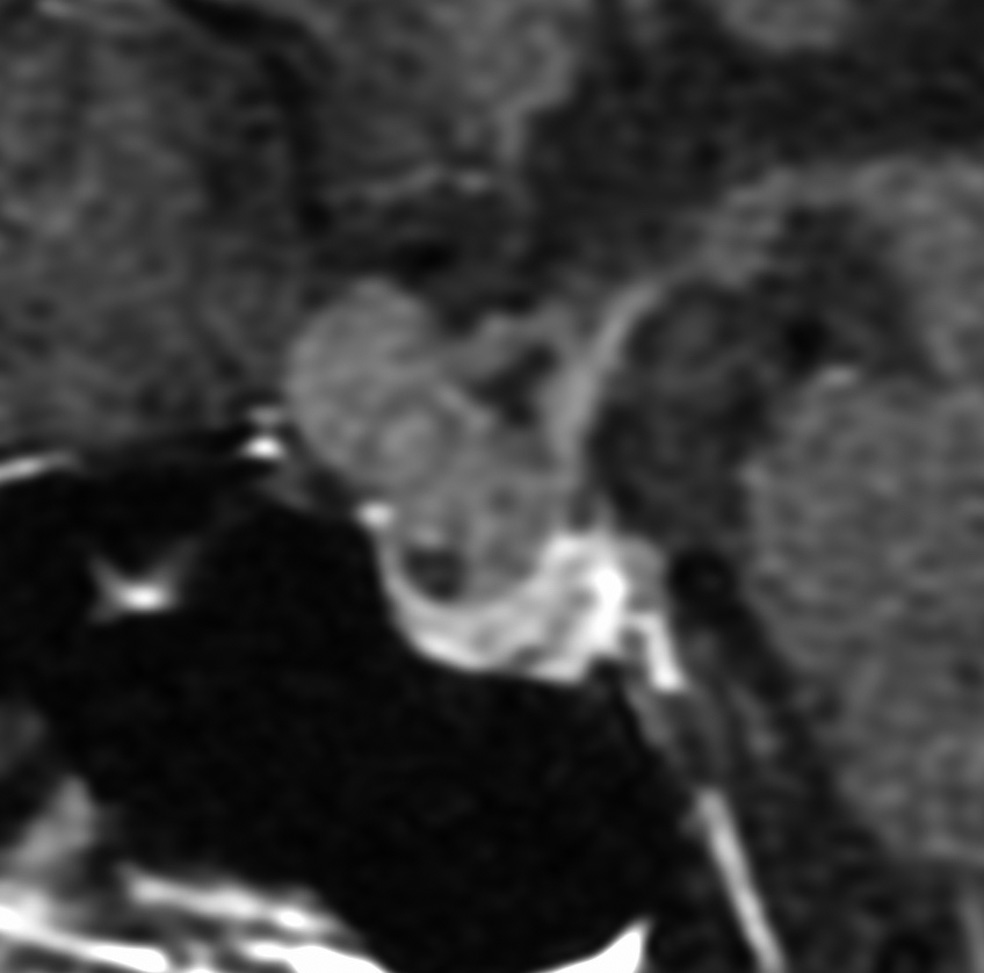

典型的な神経腸嚢胞 neurenteric cyst

左のT2強調画像で等信号,中のT2*で高信号,右はCISS画像です。

T1強調画像では,のう胞周囲の高信号の部分は半固体で,中心部の高信号はドロドロの粘液でした。基本的にガドリニウム増強はされません。まれに薄い膜状に一部が増強されることがあります。

境界明瞭は袋状の腫瘍です。椎骨動脈や脳底動脈を包み込むようにふくらんでいます。

左外側後頭下開頭という小さな開頭手術だけで全摘出しました。術後は幸い何の症状も出ていません。この例は脳幹部に食い込まないもので,運良く全摘できたのですが,そうはいかないものもあります。